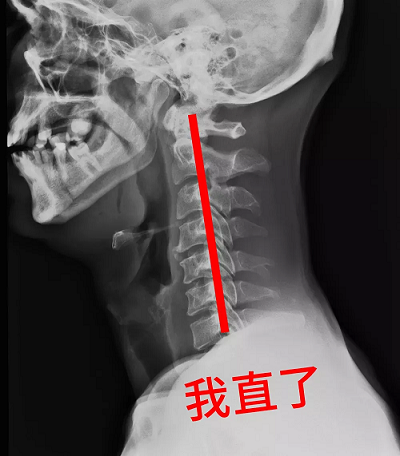

科學來講,正常人的頸椎在端坐或站立時頸椎并不是直的,而是在其中某段有一向前凸出的生理弧度,弧度就像我們的字母“C”,醫學上把這一向前的弧形凸起稱為頸椎的生理曲度。

而頸椎生理曲度變直,其實就是頸椎的“C”沒有了,變成了一條直線。短期之內,頸椎生理曲度變直不會有任何癥狀,但一段時間后就可能出現脖子疼痛、手麻,頭暈等不適。如果長期放任自流,頸椎生理曲度會越來越直,甚至形成反弓。